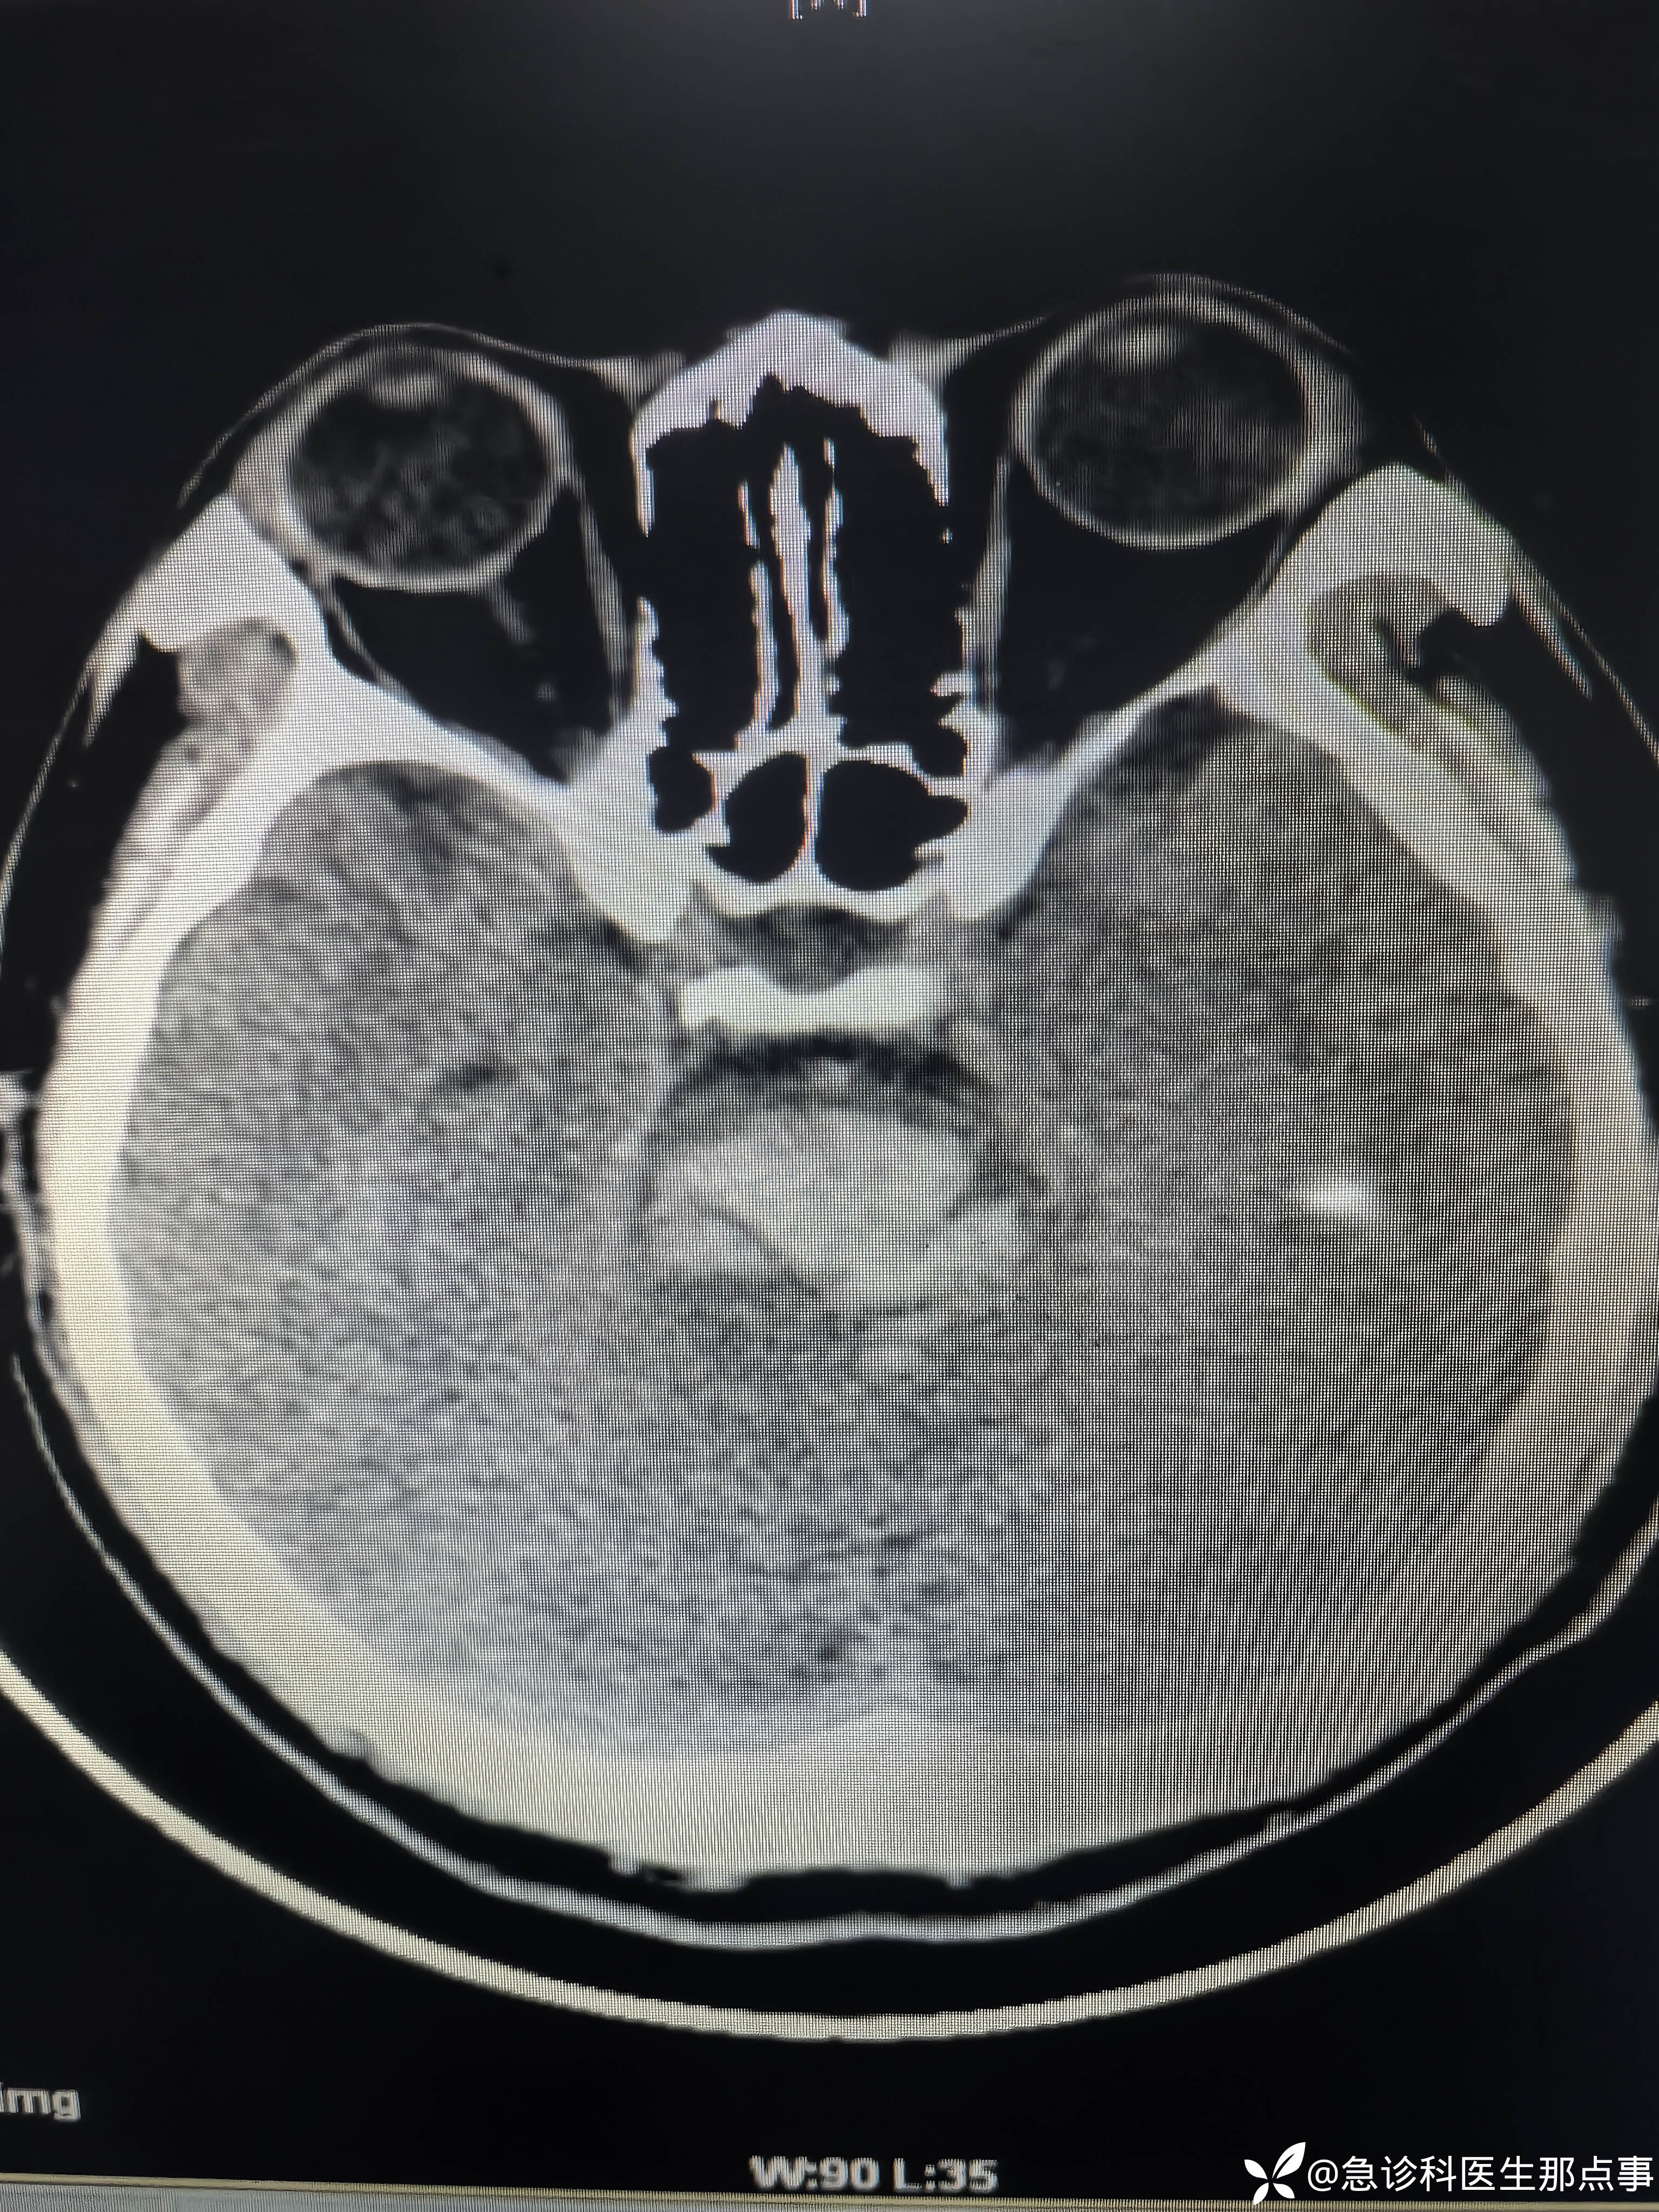

【患者信息】:男,40岁

【主诉】:突发意识不清伴双下肢间歇性痉挛抽搐半小时。

【现病史及既往史】:高血压病,间断口服药物。

【检查】:血压235/114心率82指脉氧99%意识不清,口吐白沫,双下肢间歇性痉挛抽搐。

【临床诊断】:脑干出血

【治疗经过及结果】:监护,吸氧,甘露醇快速静滴。